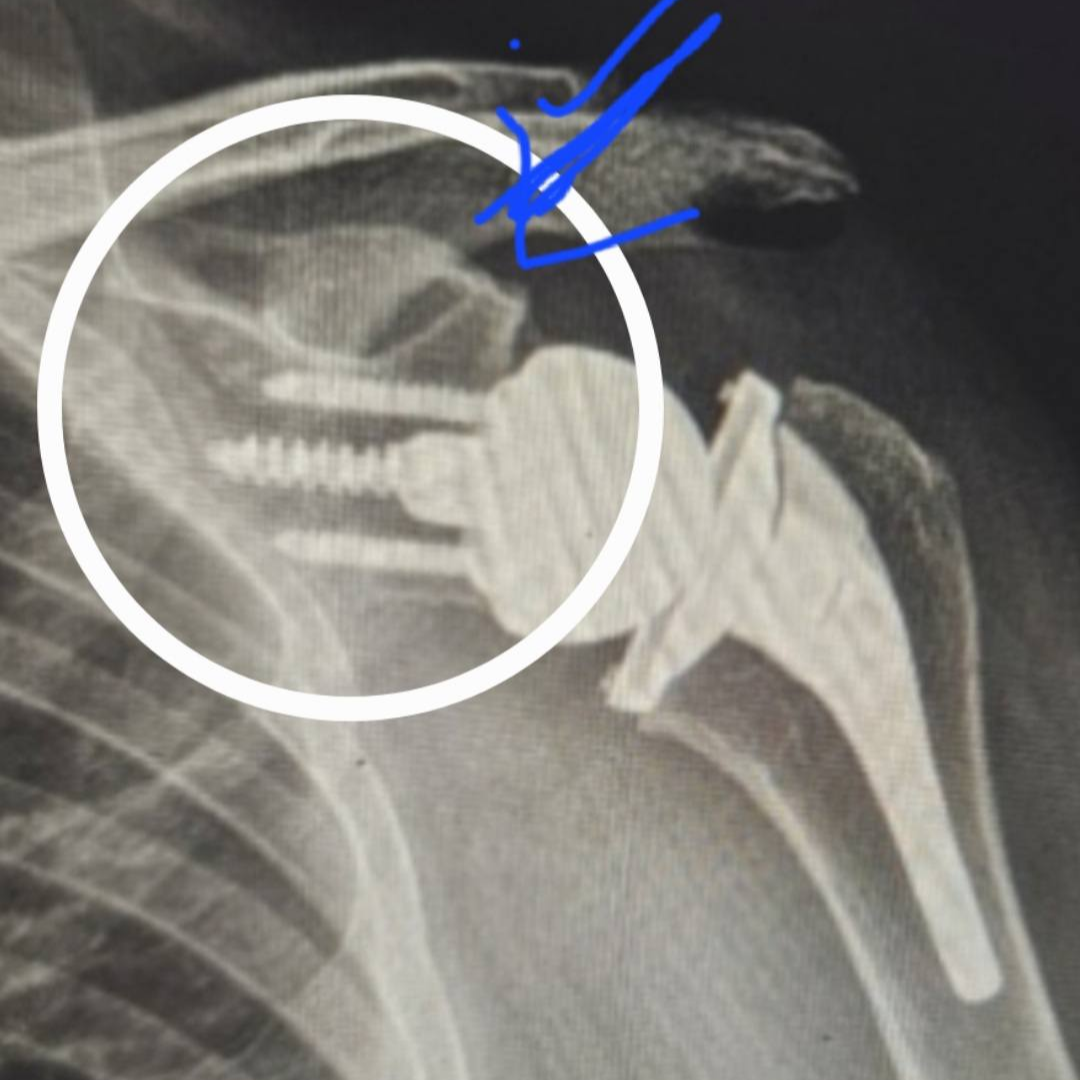

상완골 골절 핀 제거 시기

상완골 골절 핀 제거는 많은 환자들이 궁금해하는 부분 중 하나입니다. 금속 고정물은 영구적으로 남겨두는 경우도 있지만, 불편감이나 합병증 예방을 위해 제거하기도 합니다.

상완골 골절 핀 제거 기준은 다음과 같습니다.

- 상완골 골절 핀 제거 제거 시기

- 일반적으로 6개월~1년 이후

- 상완골 골절 핀 제거 제거 필요성

- 통증 유발

- 움직임 제한

- 감염 위험

- 제거하지 않는 경우

- 특별한 증상이 없는 경우

- 고령 환자

핀 제거 수술은 비교적 간단한 편이지만, 다시 회복 기간이 필요하기 때문에 반드시 의료진과 충분한 상담 후 결정해야 합니다.